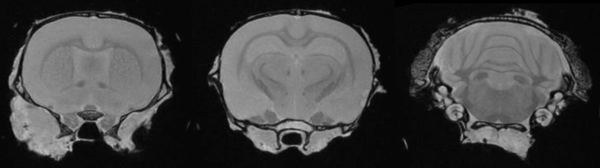

Monitoring tumor growth in the mouse brain, following the orthotopic injection of glioblastoma cells, using T2-weighted images. Image Credit: Scintica Instrumentation Inc